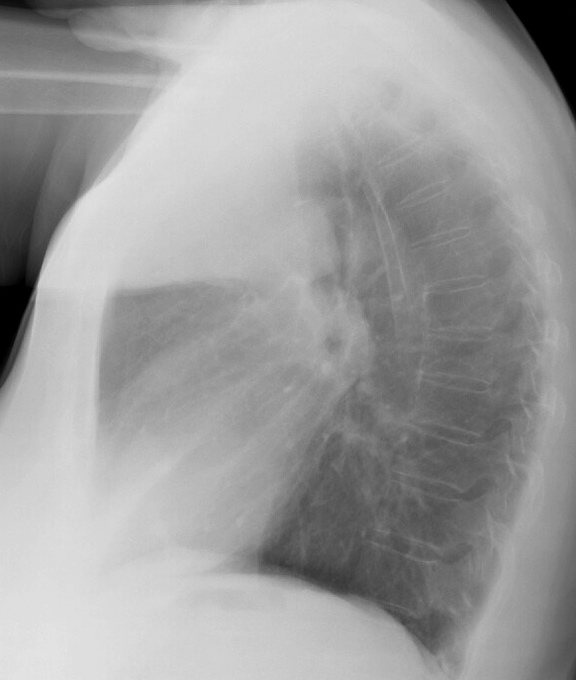

Lobar Collapse

RUL Collapse

RUL Collapse Case 8 Lat